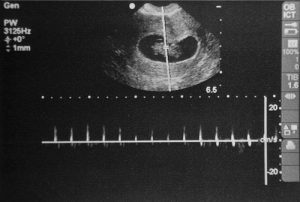

Ouvir os batimentos cardíacos do bebê é uma nova novela na vida da recente gestante. Algumas mulheres vêem tudo, saco gestacional, vesícula, embrião, porém os batimentos cardíacos não. Esse fato ocorre na grande maioria das vezes pela prematuridade do embrião. O coração do bebê começa a bater a partir de espasmos involuntários por volta da 6ª a 7ª semana de gestação2.

Por isso, não é recomendado a realização do ultrassom antes deste período, já que se corre o risco de não ver nada ou, no máximo, somente o saco gestacional. Para evitar preocupações sem necessidade, aguarde o tempo adequado.